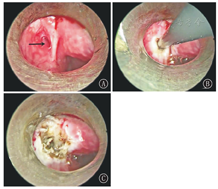

全身麻醉后,用支撑喉镜挑起会厌并充分暴露病变侧梨状窝,吸净咽腔黏液及气泡,确定内瘘口(图4)。将一次性低温等离子探头插入瘘口约1 cm,调节消融档位3,自内向外间断烧灼黏膜层(图5),每次持续消融时间1~2 s,充分破坏上皮组织。术中间断用冰水冲洗创面,减轻对周围神经损伤。检查瘘口已焦化闭合无出血(图6),退出支撑喉镜。对于急性感染期脓肿形成的病例同时行脓肿切开引流术。